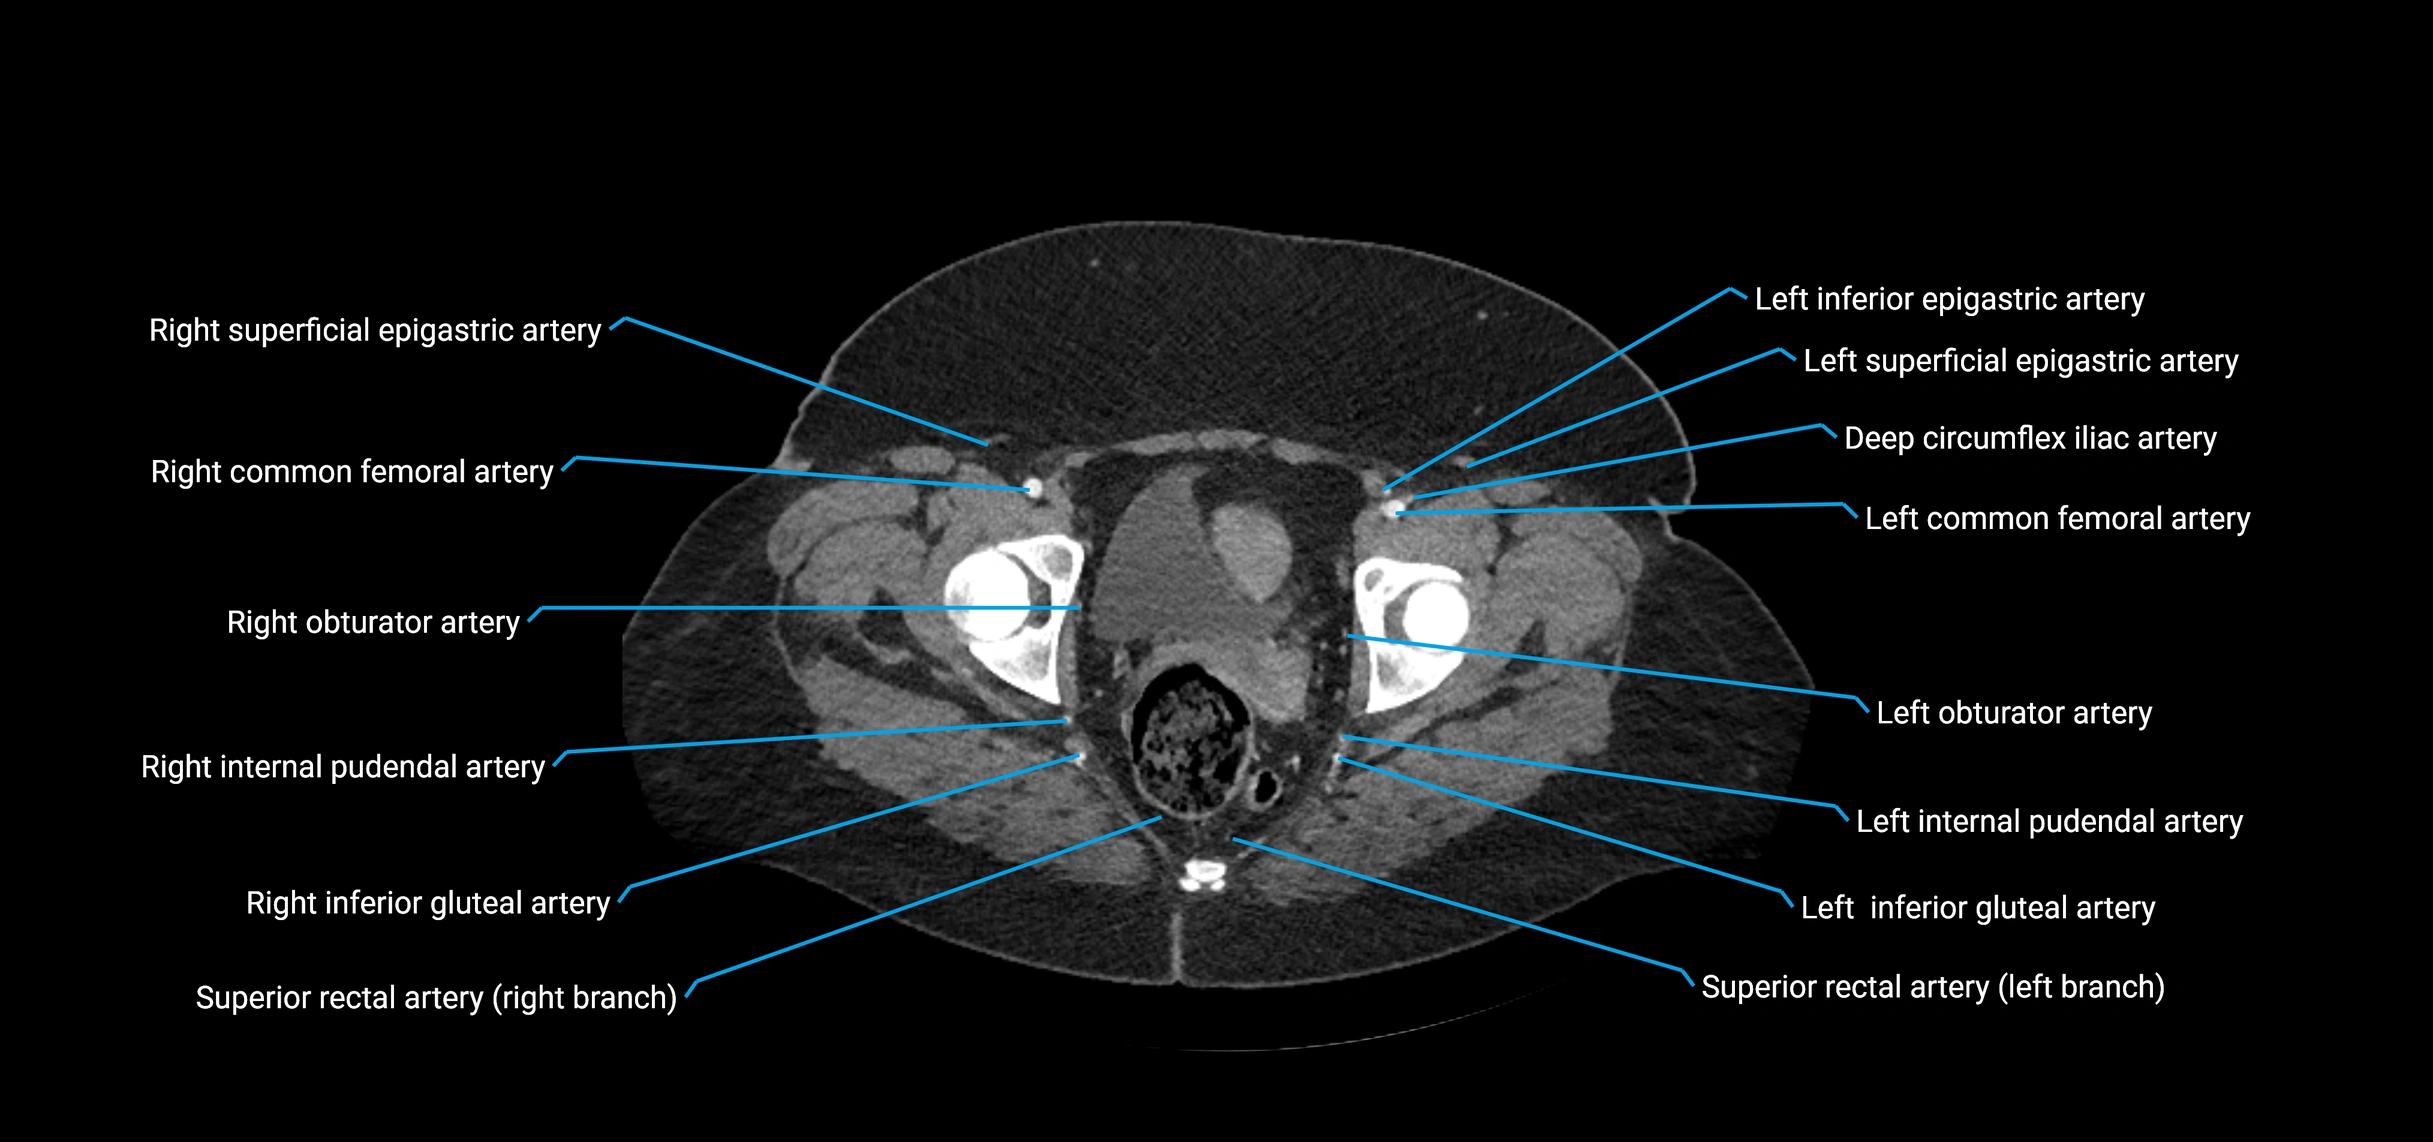

CT images

image

Contrast-enhanced CT (CTA):

• Gold standard for abdominal aortic imaging

• Provides excellent detail of lumen, wall, aneurysm, thrombus, and branch vessels

• Multiplanar and 3D reconstructions help in aneurysm measurement, stent graft planning, and dissection evaluation